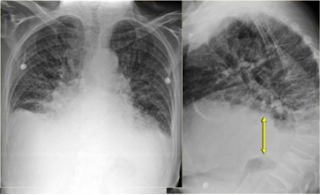

Stage III-Alveolar edema.

Prominent vena azygos dan peningkatan pelebaran pedikel

vaskuler (anak panah merah); konsolidasi perihilar dan

bronkogram-udara (anak panah kuning); cairan pleura

(anak panah biru); bayangan

jantung membesar (kepala panah merah)